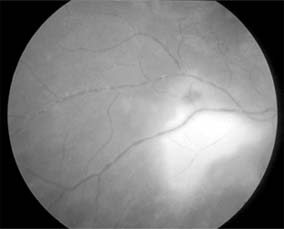

Ocular tuberculosis results from endogenous spread from systemic foci. The incidence of eye involvement is less than 1% in known cases of pulmonary tuberculosis; granulomatous panuveitis and retinal "cold" abscesses may occur (Figure 15-24). There has been a recent increase in the incidence of tuberculosis as a result of the spread of AIDS infection.

Figure 15-24

Figure 15-24: Tuberculosis. Cold abscess. A young man presented with a swelling on his back (left) and a choroidal lesion (right). Aspiration of the abscess revealed Mycobacterium tuberculosis.